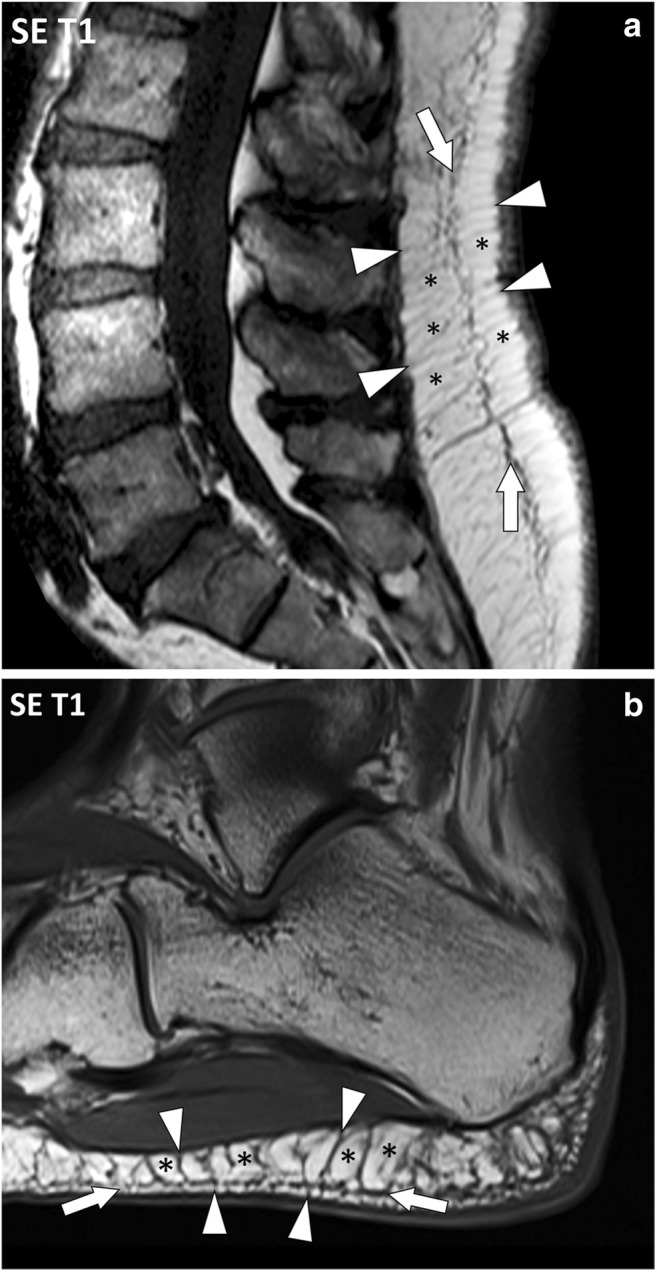

Fig. 8.

Sagittal SE T1-weighted images of (a) the lumbar spine and (b) the heel of two different patients. The fascia superficialis (arrows) is well depicted with fibrous tracts (arrowheads) perpendicular to the dermis and to the deep peripheral fascia, delineating fat lobules (asterisks). These attachments vary according to the considered body segment